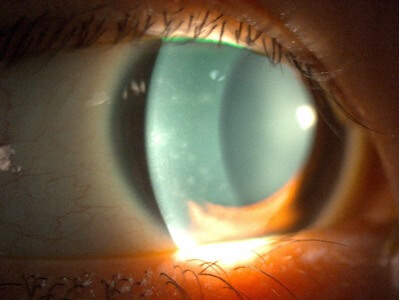

隱形眼鏡引起的角膜磨損

照片由香港理工大學眼科視光學院提供

視力下降後隱形眼鏡感染

照片由香港理工大學眼科視光學院提供